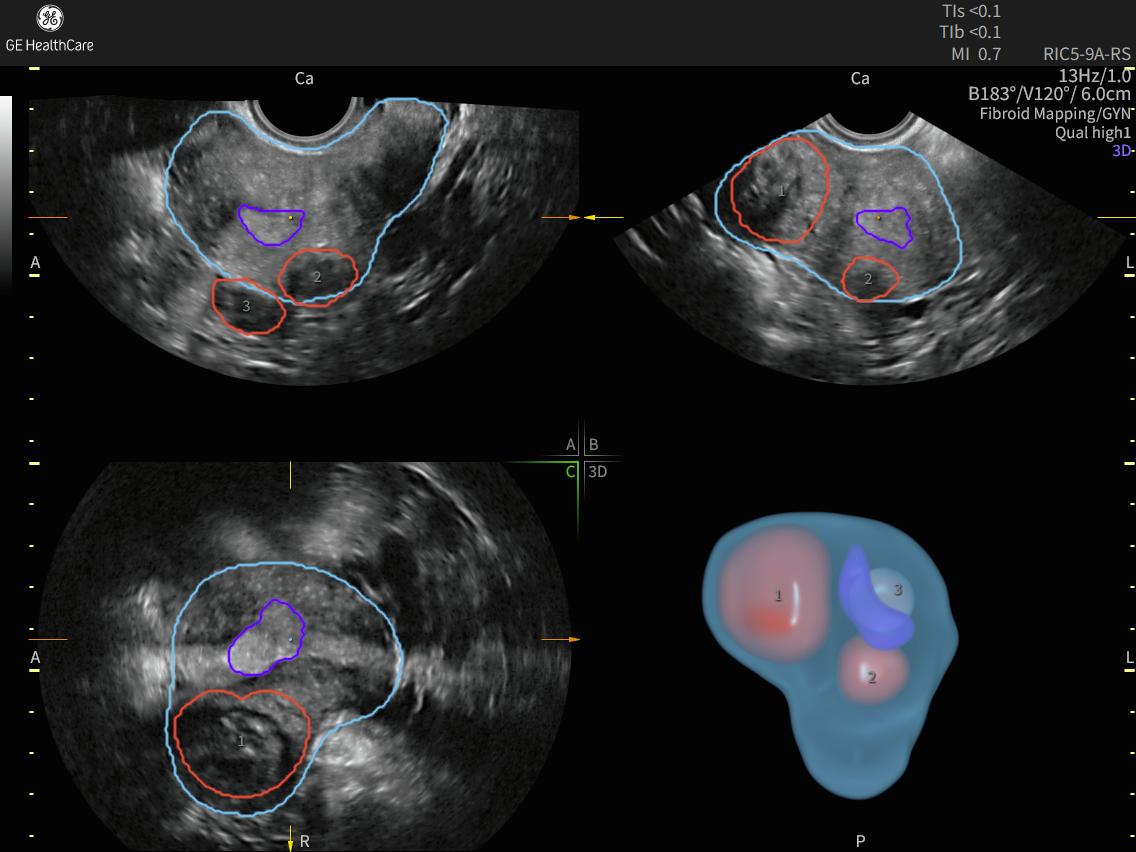

Fibroid Mapping uses AI to standardize and streamline fibroid documentation by mapping, measuring, and classifying fibroids. Fibroid Mapping can successfully segments fibroids with 88% accuracy.